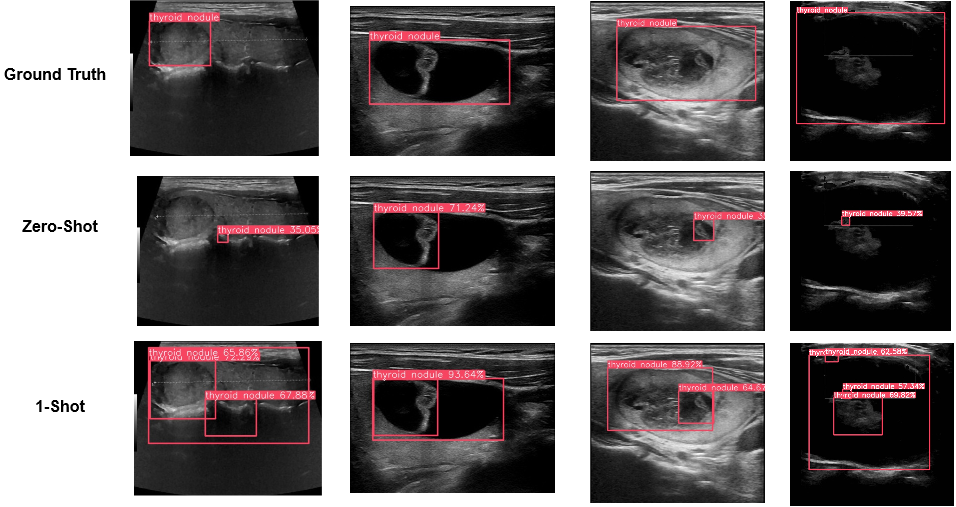

In this section, we provide some visualized examples to illustrate how attribute injection in prompts could affect the object detection for novel objects. In Figure 8, as we include more expressive attributes to the prompts, the predicted bbox can locate the target objects more accurately and confidently.

As demonstrated in Figure 9, we have shown several images and the predicted bounding boxes under the zero-shot setting on the TN3K dataset. As mentioned before, we directly use the class label as the text prompts for the radiology data, and, in this case, we simply use the ‘thryoid nodule’ to prompt the pre-trained VLM. As one can see, since the word ‘nodule” in the prompt has the language meaning of “small rounded or oval object…” in some context, the predicted bounding box in the zero-shot examples mostly aligned with the salient circle areas in the images. So, these examples prove our presumption that the unseen concept in radiology is too far different from the general image domain, and we need to provide extra visual examples to fine-tune the VLMs.

In Figure 10, we demonstrate a series of images and predicted bounding boxes for 1-shot tasks. As illustrated in the figure, the VLM can quickly understand the pattern of “thyroid nodule”, an unseen medical concept, even under a 1-shot setting. We believe the alignment of the visual and language features in the hidden space contributed to such domain-transfer capability of the VLMs. Therefore, even with a single example, the VLM can quickly map the visual features in the example to the given text prompt, and such text prompt can elicit the corresponding visual features during the test time, resulting in a much better performance.